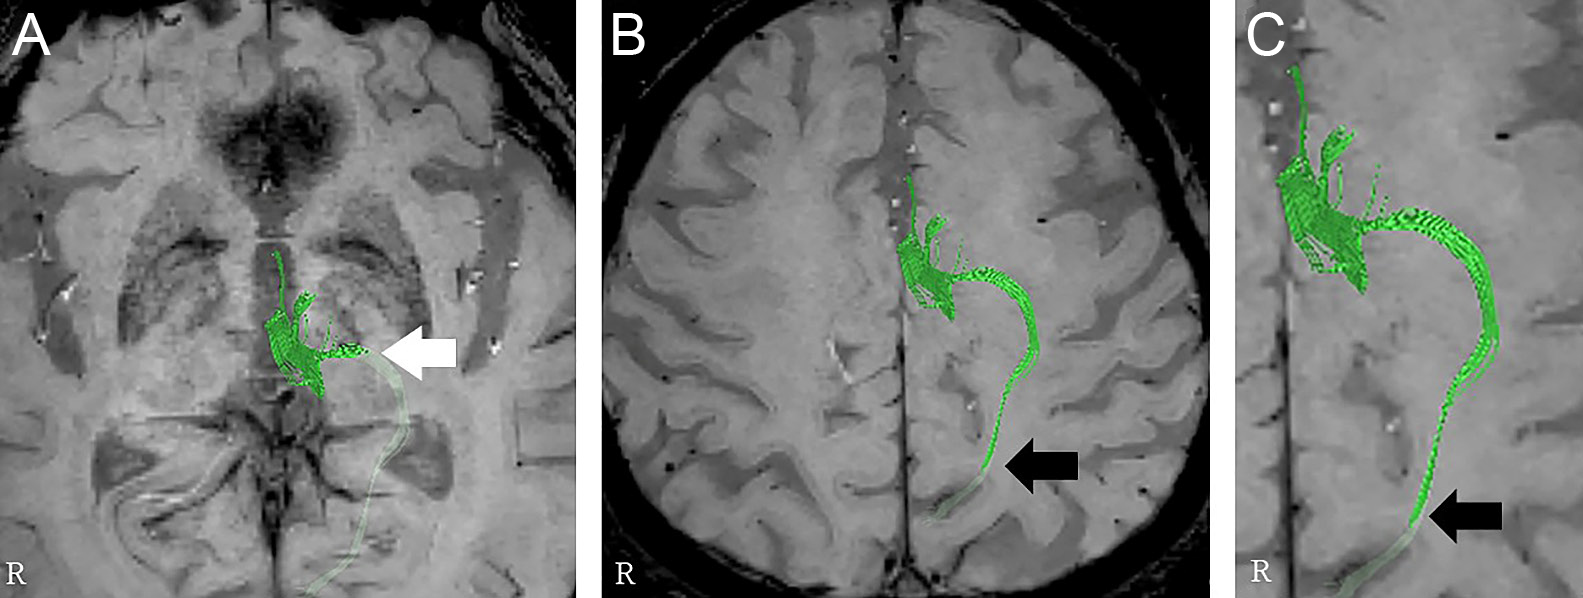

Shrimp signが診断に有用であった小脳限局型HIV関連進行性多巣性白質脳症の1例

A case of cerebellar-limited HIV-associated progressive multifocal leukoencephalopathy diagnosed with the aid of the shrimp sign

小塩 媛子, 黒田 岳志, 野原 哲人, 松岡 馨, 和田 隆秀, 村上 秀友

Himeko Ojio, Takeshi Kuroda, Tetsuhito Nohara, Kaoru Matsuoka, Takahide Wada, Hidetomo Murakami

2026/03/11